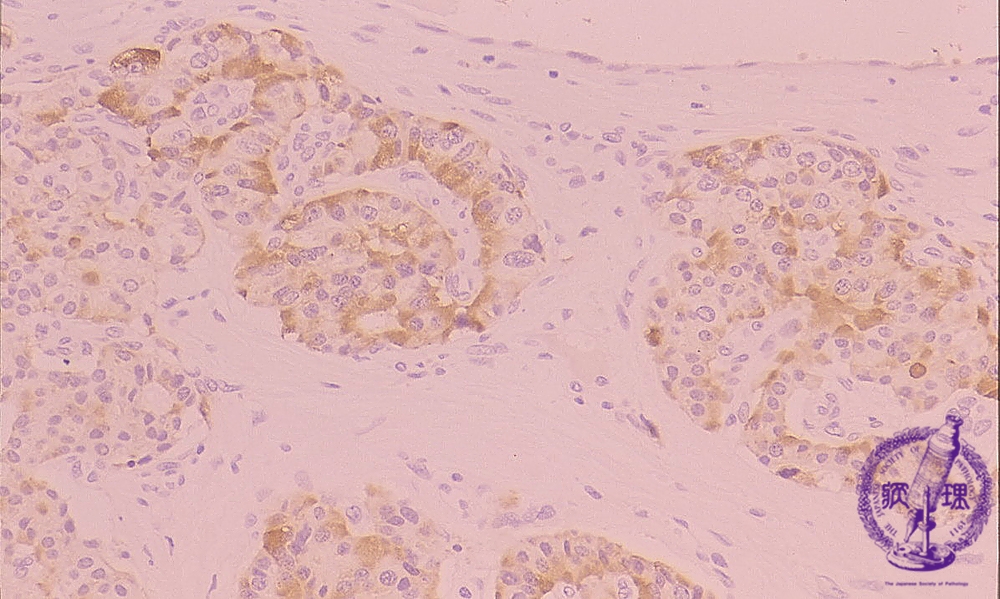

Microscopic findings (immunohistochemistry, high power view). The tumor cells are positive for chromogranin immunoreactivity (one of the key markers for neuroendocrine cells).